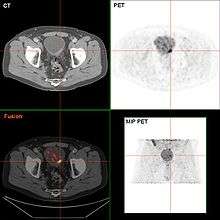

- N1 Metastasis in a single lymph node 2 cm or less in greatest dimension

- N2 Metastasis in a single lymph node more than 2 cm but not more than 5 cm in greatest dimension,or multiple lymph nodes, none more than 5 cm in greatest dimension

- N3 Metastasis in a lymph node more than 5 cm in greatest dimension